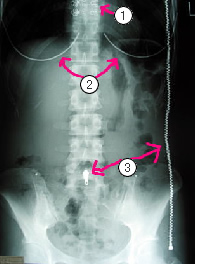

下の写真はお腹の写真です。

①②③のところを注目してください。

①と②はブラジャーをしたまま撮影されたことがわかります。

③は服のチャックです。

ブラジャーにしろ、チャックにしろ、金属は写真にこんな感じに写ってきます。皆さんもお気づきのようにこれでは患者様の体の情報が隠れてしまいます。せっかく写真を撮ってもこれでは意味がありません。

体調不良で来院している患者様には辛いこととは思いますが、検査着への着替えや服の脱衣のご協力をお願いします。